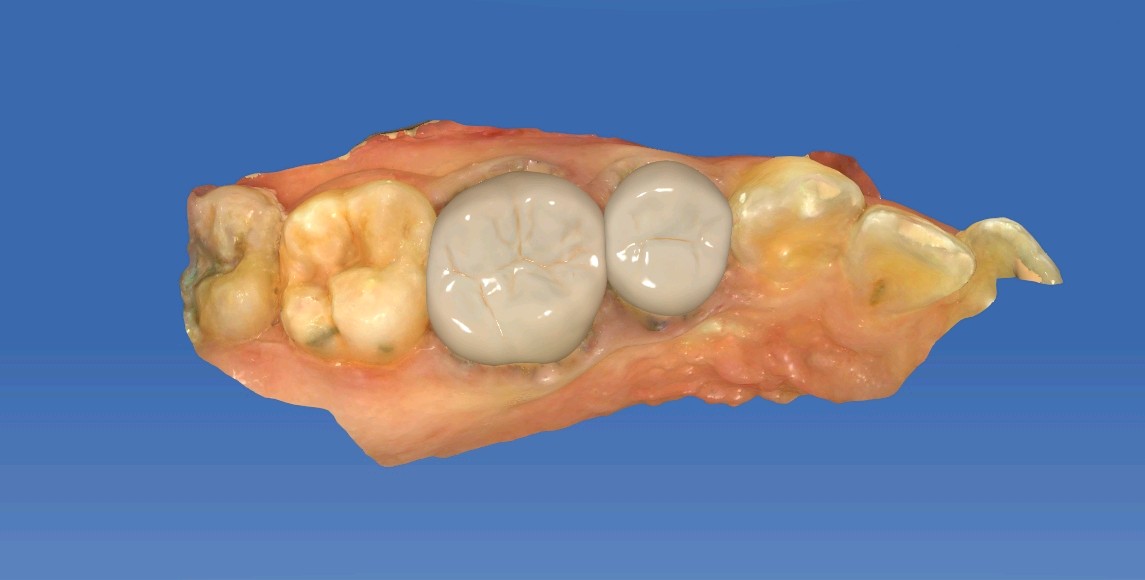

嵌体是在口外石膏模型上由专门的牙科技师制作出来的,然后再由临床医生将其戴入患者口内,最终粘固形成。

嵌体的整个的制作过程完全避免了在口腔内部操作的干扰因素,这就使得嵌体的制作比传统的补牙要更精细;

边缘密合性好、咀嚼备感舒适,避免了传统补牙容易脱落、嵌塞食物并造成继发龋等问题;

易清洁邻面可高度抛光,形成良好的邻接关系。光滑的抛光面容易清洁,可以减少菌斑的附着;良好的耐腐蚀性,耐磨性陶瓷可以留存在世间数千年而不腐蚀,故用瓷材料做为嵌体就不存在腐蚀问题;

极佳的生物相容性和美学效果这是全瓷的特性,不存在所谓的金属过敏现象,全瓷的美学效果非常显著;